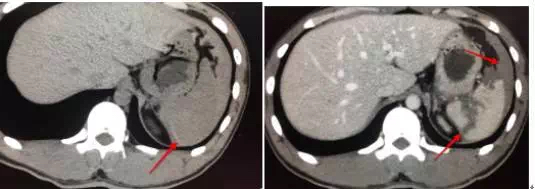

28岁女,车祸入院,怀孕三个月,平扫密度不均匀,增强很大的撕裂口,保守治疗后好转。20天后做了清宫手术。

3.轻微撕裂伤,平扫难以发现,要做增强,就算夜班,也要做增强。

18岁男,车祸入院,平扫脾周积液,高密度,边缘见条状高密度影,脾脏积血(看到此征象,夜班急诊的时候千万要警惕脾破裂,及时提示临床医生,患者随时都有可能大出血休克)。CT增强可见脾破裂,破口及积液显示较平扫清晰。